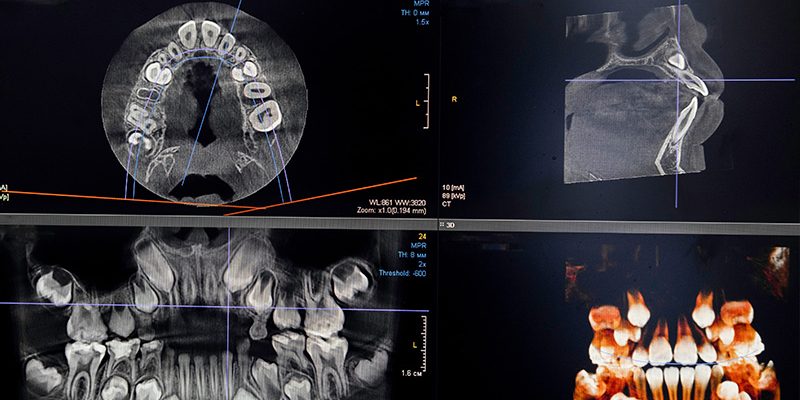

Präzise Diagnostik mit Digitaler Volumentomographie (DVT)

Wir bieten Ihnen außerdem die modernste Diagnosetechnik mit der Digitalen Volumentomographie (DVT) an. Mit diesem präzisen 3D-Röntgenverfahren erhalten wir detaillierte Aufnahmen Ihrer Zahn- und Kieferstruktur, die uns bei der optimalen Planung und Durchführung Ihrer Behandlung unterstützen. Lassen Sie sich gern ausführlich zu den Vorteilen der DVT beraten.